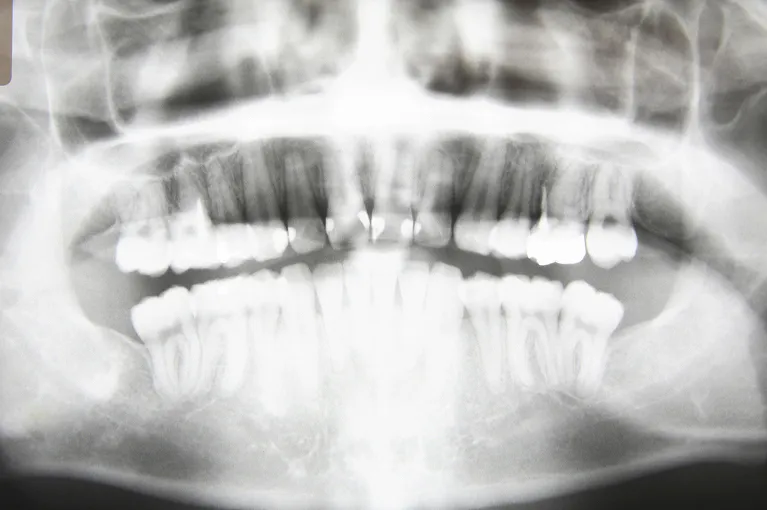

歯や顎の骨を断面撮影できるデジタルパノラマX線などを使用し、現状の口腔内の状態を検査し、その結果をもとに治療計画を立てます。

当院では歯や顎の骨を断面図で詳細に診断できるデジタルパノラマX線など、各種の高性能機器を揃えており、より正確で緻密な診断ができる環境を整えております。